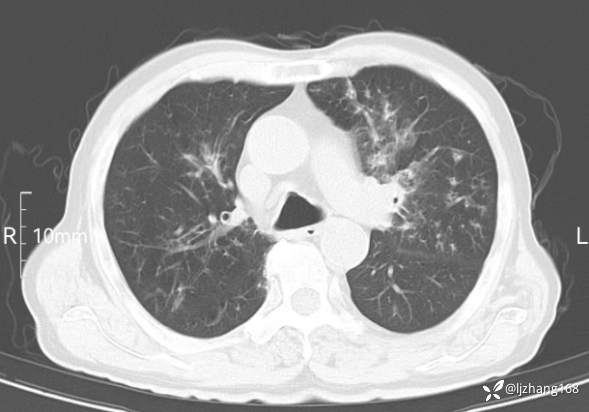

辅助检查:胸部CT:双肺肺气肿,间质性病变,血气分析:PH 7.413, PCO2 29.2mmHg, PO2,81.8mmHg,乳酸 3.3mmol/1,剩余碱-4.0mmol/1,HC03 18.8mmol/1。全血超敏C反应蛋白:超敏C反应蛋白 135.60 mg/L、 白细胞 14x19^9/L,中性粒细胞11.6x10^9/L。